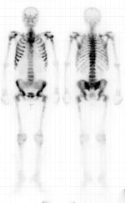

正常骨显像

全身多发骨转移

超级骨显像

肺性肥大性骨关节病